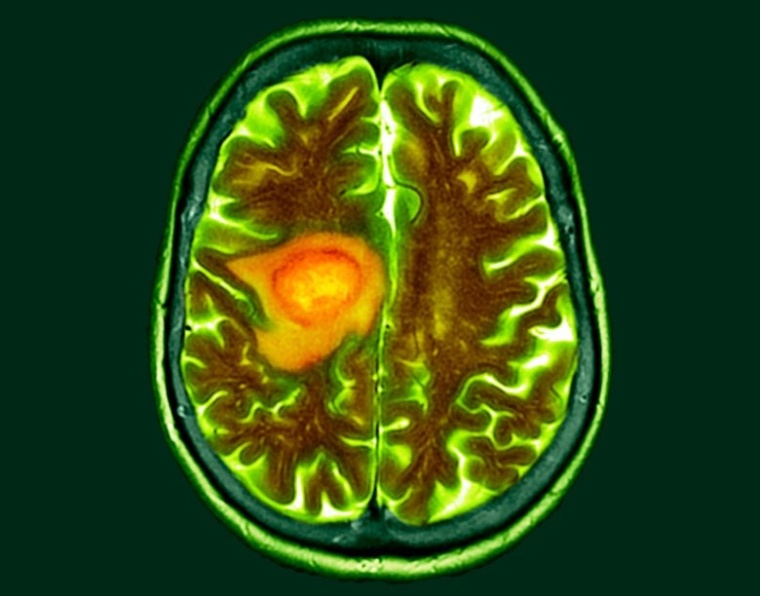

Neuer Ansatz für eine T-Zell-Immuntherapie gegen bösartige Hirntumoren

Forscher am Deutschen Krebsforschungszentrum (DKFZ) und an der Universitätsmedizin Mannheim (UMM) haben eine vielversprechende zelluläre Immuntherapie zur Behandlung von Glioblastomen entwickelt.

Zelluläre Immuntherapien haben sich bei der Behandlung verschiedener Formen von Blutkrebs teilweise als sehr erfolgreich erwiesen – scheitern aber bislang an soliden Tumoren. Dies gilt insbesondere für Glioblastome, aggressive Hirntumoren, die durch die Blut-Hirnschranke zusätzlich vor der Invasion therapeutischer Zellen geschützt und daher besonders schwer zu behandeln sind.